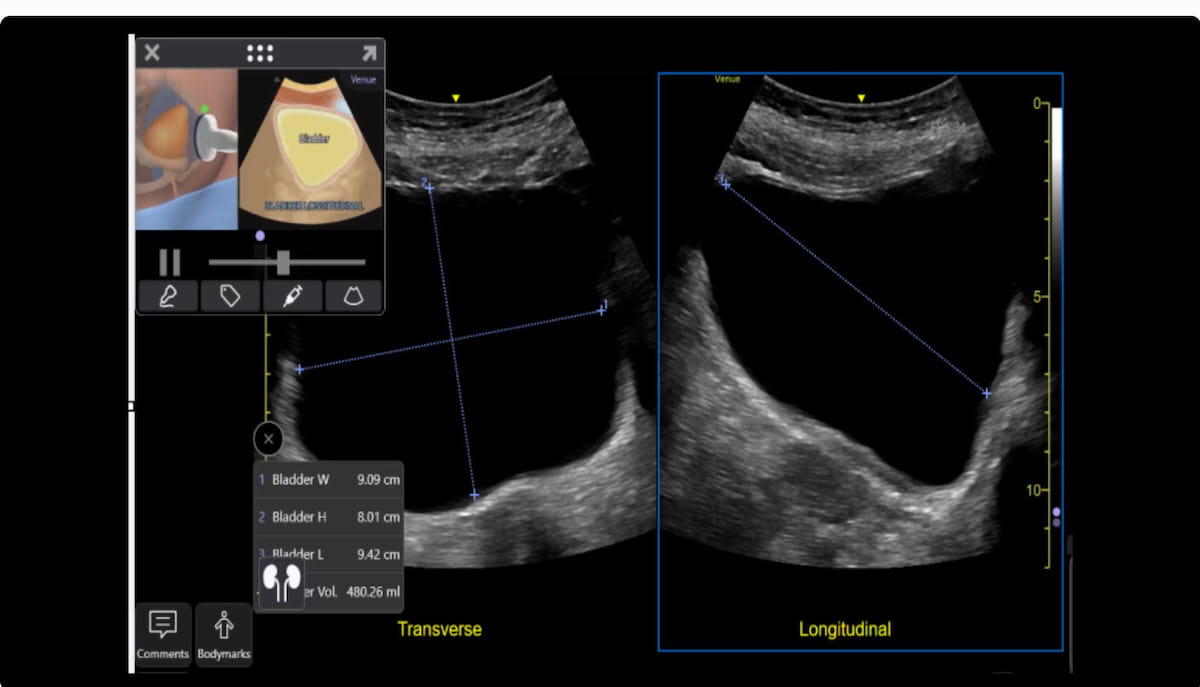

Enhanced assessment tools for myocardial strain, urinary bladder volume and contrast-enhanced abdominal views are among the new features for the updated Venue point-of-care (POCUS) ultrasound systems from GE HealthCare.

The company said the Automated Function Imaging feature enables objective evaluation of myocardial strain and Nerveblox™ provides automated anatomical labeling to streamline 12 common peripheral nerve blocks.